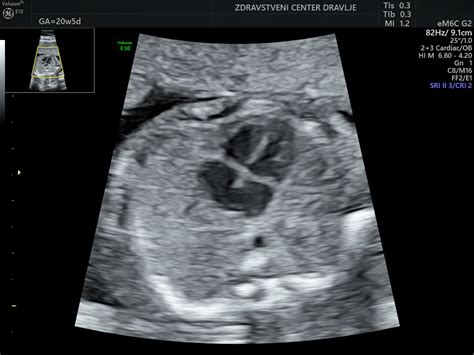

Ultrazvok in Genetski Pregledi: Pogled v Prihodnost

Dvanajsti teden nosečnosti je pogosto čas za prvo pomembno ultrazvočno preiskavo, ki je znana tudi kot pregled nuhalne svetline (NT pregled). Ta natančna preiskava omogoča:

- Potrditev Starosti Nosečnosti: Natančnejši izračun pričakovanega datuma poroda.

- Ocena Tveganja za Kromosomske Nepravilnosti: Zdravnik preveri procentualno možnost za določena genetska stanja, kot je Downov sindrom.

- Pregled Razvoja Ploda: Preveri se razvoj ključnih organov in telesnih značilnosti.

Trenutno je določitev spola dojenčka še vedno težka zaradi nezadostne razvitosti anatomije. Natančnejšo informacijo o spolu bo zdravnik verjetno podal na pregledu v 20. tednu (morfologiji). Če vas spol zelo zanima, se lahko odločite za krvne teste, ki lahko nudijo tudi to informacijo.